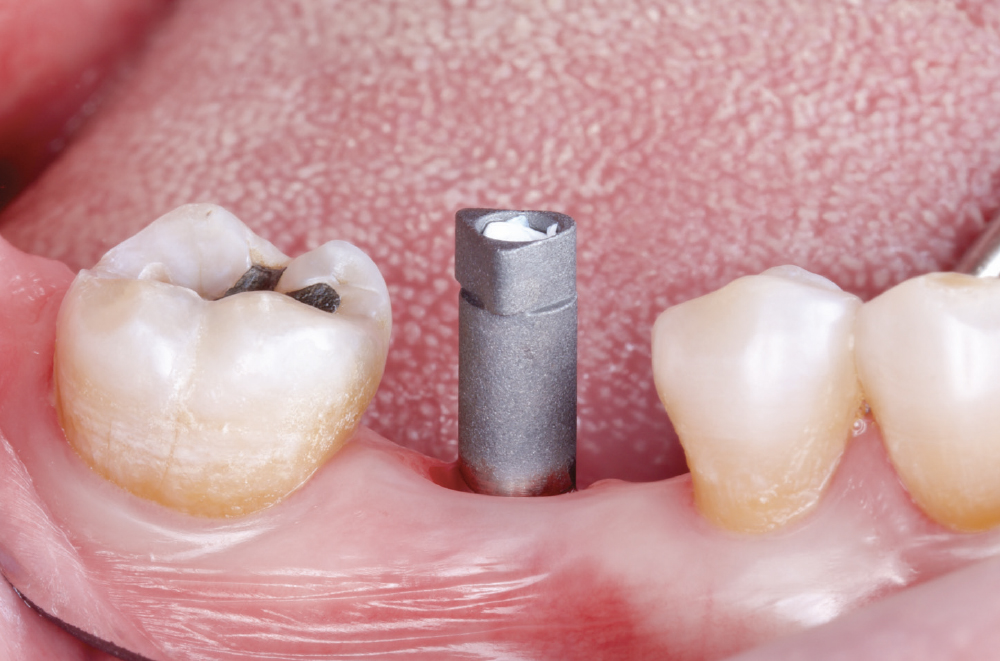

Verify Complete Scan Body Seating

Verify Complete Scan Body Seating. Confirm the scan body is fully seated to the implant before scanning — how it seats is precisely how the final restoration will seat. Use a radiograph if there is any question about complete seating, as an incompletely seated scan body will result in a restoration that does not fit, regardless of scan quality. Apply firm finger pressure or use a seating instrument, then verify there is no rocking or movement. Check for any tissue interference preventing complete seating and address it before scanning.

Capture the Surrounding Soft Tissue Immediately

Capture the Surrounding Soft Tissue Immediately. Scan the peri-implant soft-tissue architecture as soon as the scan body is placed, before the tissue collapse occurs. Gingival tissues begin to collapse and distort within minutes of scan body insertion, and the initial tissue contours are critical for creating proper emergence profiles. Work efficiently but thoroughly to document the tissue topography in its most accurate state.

Implant post in socket